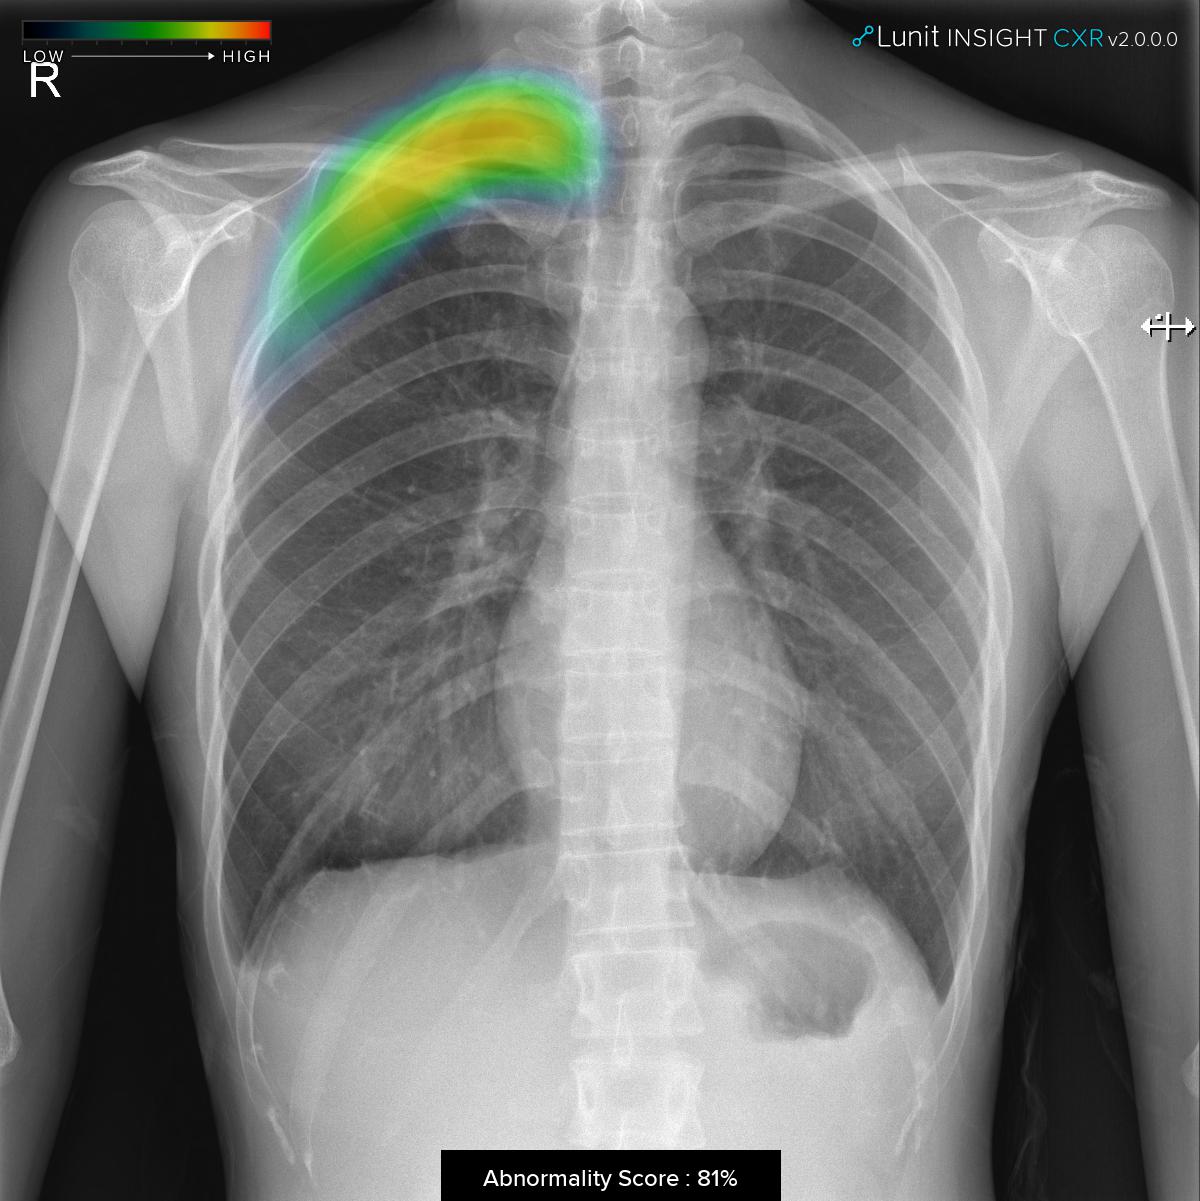

The software analyzes chest x-ray images within seconds, providing an indication of the location of lesions suspicious for major lung abnormalities such as nodule, consolidation, and pneumothorax. An abnormality score of the detected lesion is also shown with the location information.